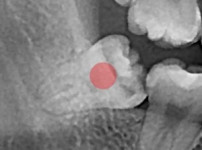

충치가 심한 사랑니